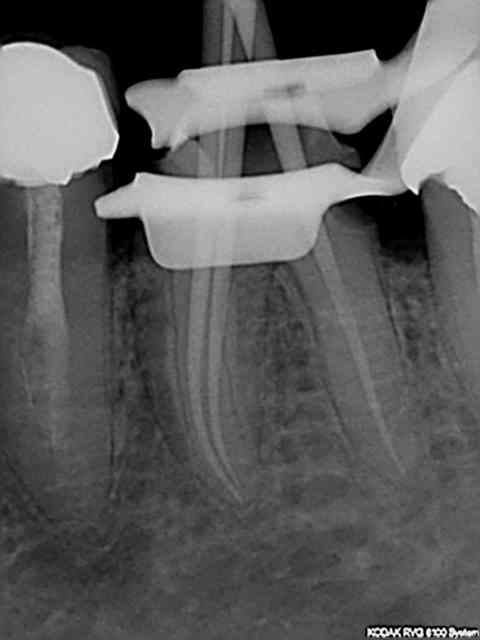

La nomenclature a aussi beaucoup changé en 30 ans a tel point que je suis complètement largué avec ces histoires de Z6 + Z3+ Z3 Je ne sais pas coter ces radios la radio de départ (dite de diagnostic) faisant partie d'un status pris un autre jour mais sur lequel j'avais coté la 47 et la 44 mais pas la 46.))))))